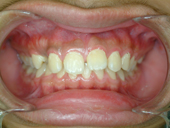

圖一、嚴重空間不足導致虎牙

圖二、經過拔牙及矯正治療

導致牙齒排列不整的原因包羅萬象,情況也是千奇百怪。有的人是因為牙齒大小和牙床大小不諧調,導致齒列擁擠(圖一、二)或是產生縫隙,台灣人最介意的“牙齒漏財”即屬於縫隙這個類型(圖三、四);有的人則是牙齒長到不該長的位置而沒有冒出牙床(圖五、六);有些人則是上下顎骨發育不諧調,導致戽斗(或稱月亮臉)或是鳥臉的狀況;除此之外,暴牙、先天缺牙、多生牙、後天蛀牙或長期缺牙導致相鄰牙齒東倒西歪、車禍外傷導致牙齒移位或喪失牙齒(圖七、八)、牙周病所導致的門牙散開…等等,都是齒顎矯正的適應症。